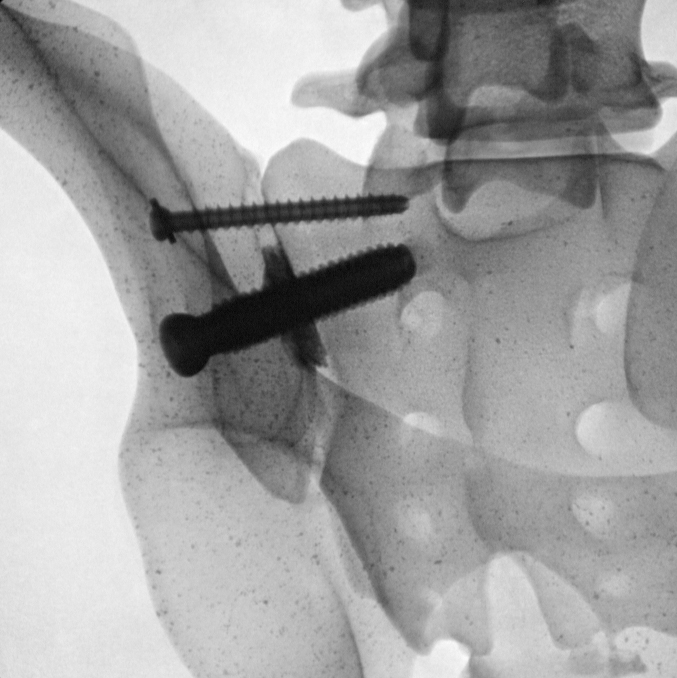

For all my website subscribers and readers, I offer you my new page on the Zyga SImmetry® – True SI Joint Arthrodesis (fusion) surgical option for Sacroiliac Joint Instability/Dysfunction (SIJD) and Pathology. I cannot not personally recommend this procedure as I do not have direct experience with it; however, as a fusion alternative to my Stryker Cannulated Screw Fixation without fusion procedure done for my diagnosis code: 724.6-Disorders of the Sacrum , I do recommend this product for those that need a fusion over screw fixation only. I do have the permission of my Northwest Zyga Representative to use their content here on my website and I feel honored to do so. (Click on images to enlarge)For more in depth information on this surgical procedure, here is a Dove Press Journal on Medical Devices: Evidence and Research published article authored by Larry E. Miller and Jon E. Block entitled:

Minimally invasive arthrodesis for chronic sacroiliac joint dysfunction using the SImmetry SI Joint Fusion system